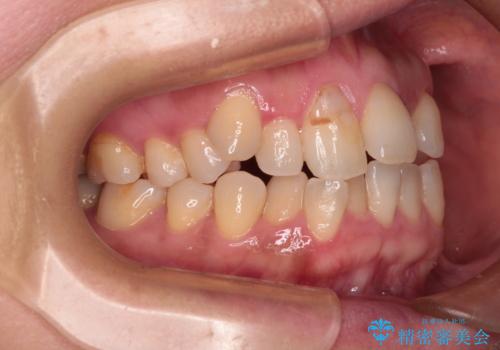

下顎骨が左側にズレて成長してしまったため、左側の咬み合わせが上下反対になっている状態でした。

そこまでの処置は望んでいらっしゃらなかったため、歯列矯正でのカムフラージュにより咬み合わせを改善することとしました。

予想通り左側の咬み合わせの調整に苦労をしましたが、最終的には違和感のない咬み合わせを達成することができました。